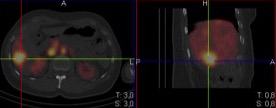

Radionuclide imaging with labeled red blood cells

Types of tests: SPECT/CT of the liver

Aim: to verify the nature of an identified neoplasm of the liver. To make of a differential diagnosis of hemangioma, metastases and primary neoplasms. To detect and localize intermittent hemorrhage in the small intestine and colon.

SPECT/CT allows identification and location of lesions that are less than 1 cm. It allows location of the source of bleeding in the intestine.